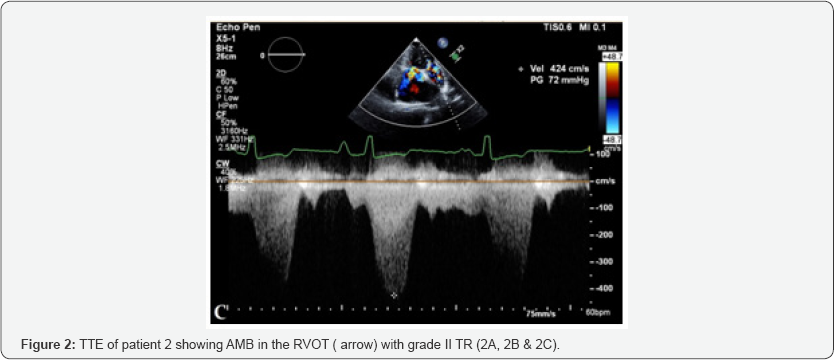

All patients underwent detailed echocardiography, pulmonic valve was normal in all patients. Cardiac catheterization and catheterization was done in all patients, Figure 1 showing cath of Patient 1. Figure 1-3 showing echo findings of patient 1, 2 & 3. Echocardiography and catheterization findings are shown in Table 2.